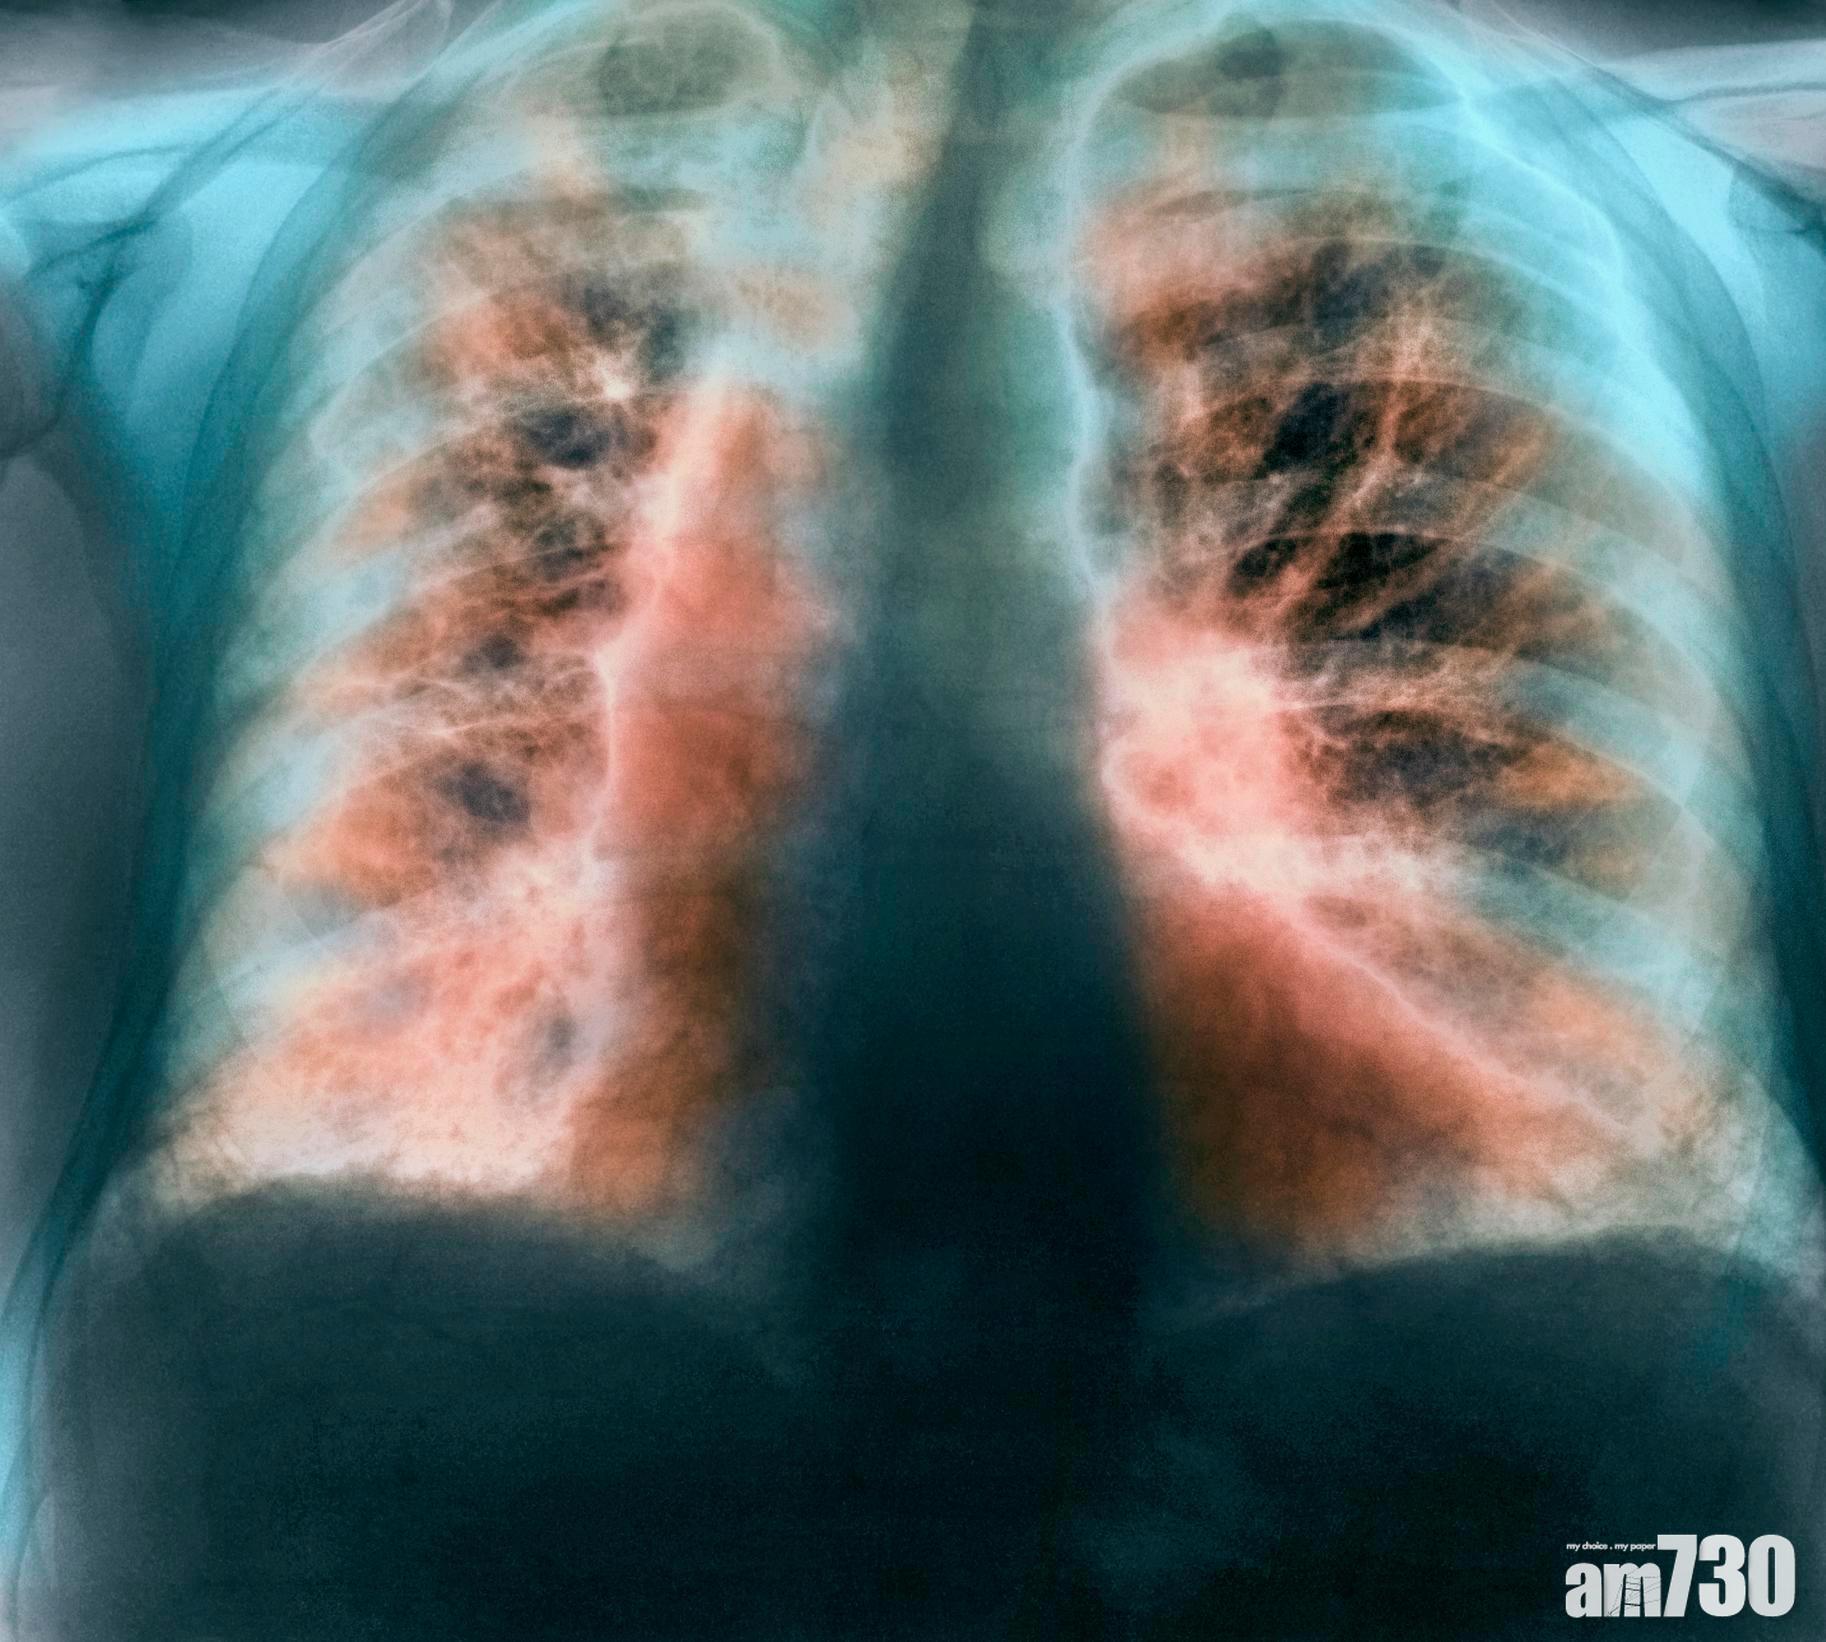

英國有研究表明,睡眠時間過長或不足,患上肺纖維化病風險高3倍。(互聯網圖片)

都市人工作不定時,經常要輪更甚至通宵工作,從而擾亂睡眠的生理時鐘。最近英國一個跨學府研究團隊,就發現經常睡眠時間超過11小時,或少於4小時的人,比有著正常睡眠規律(即一天睡眠7小時)的人,患上存活率低,不可逆轉的呼吸道疾病「特發性肺纖維化」Idiopathic Pulmonary Fibrosis的風險高出2至3倍,研究人員認為關聯正歸因於人體時鐘。相關研究已發表於《美國國家科學院院刊》上,由曼徹斯特大學、牛津大學、紐卡素大學、倫敦大學學院和多倫多大學所組成的團隊共同研究。

這種病因不明,但持續地肺間質因廣泛纖維化而造成的肺組織增厚,最終令肺部喪失正常氧氣交換功能的致命疾病「特發性肺纖維化」,估計在英國每年造成約5,000人死亡,與患白血病死亡人數相若。負責今次研究,曼徹斯特大學感染、免疫和呼吸道內科專家John Blaikley博士表明,從小鼠模型發現通過改變生理時鐘機制,有可能破壞因過度修復而造成疾病的纖維化過程,為治療或預防開闢了新途徑。

「我們體內的時鐘幾乎調節著人體每個細胞,24小時循環不息地進行如睡眠、荷爾蒙分泌和新陳代謝等許多過程。」而在肺部,時鐘主要位於空氣輸送通道的氣道中。但是研究小組發現,在肺纖維化病的患者中,這些時鐘波動會延伸到稱為「肺泡」Alveoli的肺部支氣管末端小氣囊。研究人員利用英國生物銀行的人類數據表明,引致肺纖維化與睡眠時間長短有所關係。跟每天睡眠7小時的人相比,報告發現每天規律睡眠4小時或更少的人,其患肺纖維化的機會增加了一倍,至於每天睡眠11小時或更長的人,患病的機會更增加了三倍。從中團隊發現一種重要時鐘蛋白Clock Protein「REVERBα」能夠改變肺纖維化中一種重要蛋白的產生,減少患者肺片中造成問題的膠原蛋白,為醫療帶來曙光。John Blaikley博士補充,「仍然需要進一步研究來加強肺纖維化和睡眠兩者的關係,如果結果得到證實,那麼最佳時間睡眠可能會減輕這種破壞性疾病的影響。」